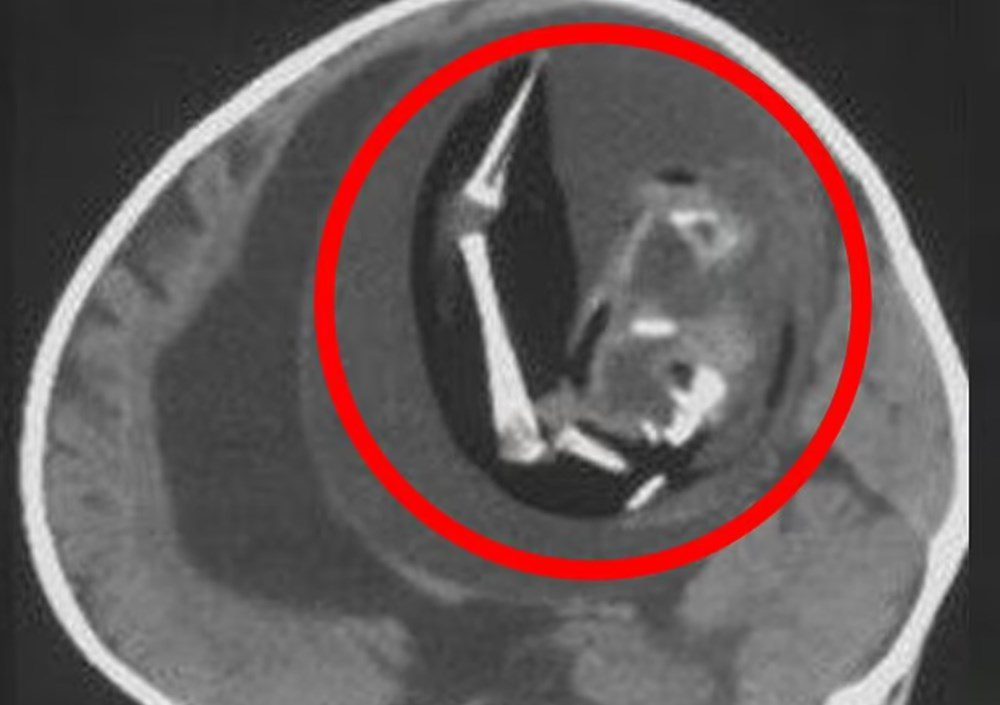

Yeni bir araştırmaya göre, Çin’de doktorlar bir yaşındaki bir çocuğun beyninde ‘doğmamış ikizinin fetüsünü’ buldu. Neurology dergisinde yayınlanan çalışmada, çocuğun motor fonksiyonlarında sorunlar yaşaması ve kafasının büyümesi üzerine ebeveynleri tarafından hastaneye getirildiği ortaya çıktı. Şangay’daki doktorlar, doğmamış ikizin fetüsünün çocuğun beyninde geliştiğini tespit etti. Çalışmanın yazarları, “Motor becerilerinde gecikmesi ve genişlemiş baş çevresi olan 1 yaşındaki bir kız çocuğunda malforme olmuş monokoryonik diamniyotik ikiz olan intraventriküler fetüs içinde fetüs (fetus-in-fetu) tespit edildi.” denildi.

Parazit ikiz olarak da adlandırılan fetüs içinde fetüs, ikizlerin rahimde yapışık olması, ancak yalnızca birinin gelişmeye devam etmesi durumunda ortaya çıkıyor. Çalışmada, genom dizilimi sonrasında fetüsün çocuğun ikizi olduğunun tespit edildiği de belirtildi.

Bununla birlikte fetüs içinde fetüs vakaları ikiz gebeliğin çok erken aşamalarında, döllenmiş bir yumurta tarafından oluşturulan ve blastosist olarak adlandırılan bölünen hücre kümesinin düzgün bir şekilde ayrılamamasıyla meydana geliyor. Ardından embriyolardan biri diğeri tarafından çevreleniyor.

Diğer ikizin çoğalan hücreleri tarafından sarılan öteki fetüs gelişemiyor, ancak kan desteği aldığı için “canlı” kalıyor.  Çalışmada, “Yapışık parçalar ana fetüsün ön beynine dönüşüyor ve nöral plak katlanması sırasında diğer embriyoyu sarıyor.” ifadeleri kullanıldı.